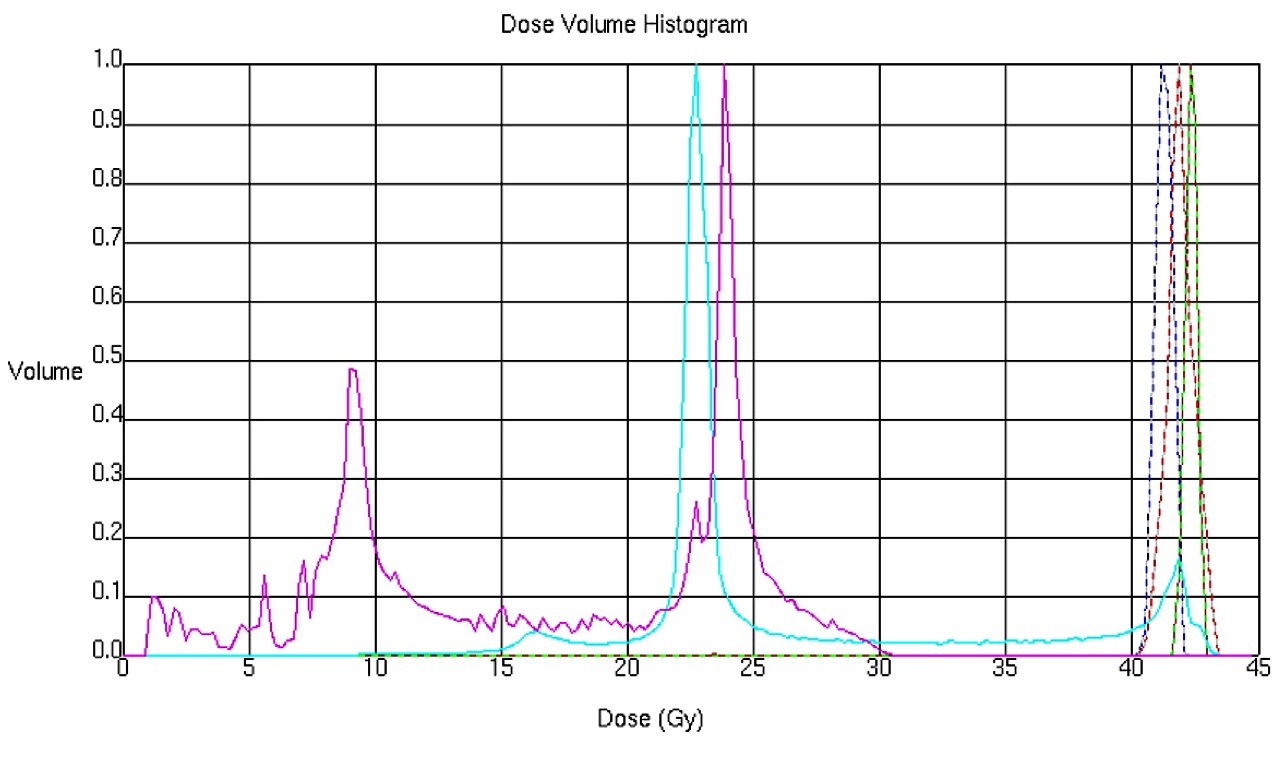

まず申し上げたいのは、最近の放射線治療は「がん」治療のかなでも副作用の少ない治療法とされています。それには多くの技術革新があっての結果ですが、一般にピンスポイント照射とも呼ばれている高精度な三次元治療計画が最も重要な役割を果たしています。それは副作用のでやすい臓器を避けて病巣に放射線を集中照射する技術です。写真4をご覧ください。

赤い肺癌に放射線照射を行うときに最も注意しなければならないのは緑の脊髄です。画像情報を駆使して、脊髄障害を起こさずに肺癌病巣に照射する方法を事前に十分検討してから、最も良い方法を選んで実際の治療を行うのです。写真5は主に食道に放射線を集中しものですが、ここでは前後にある心臓と脊髄を避けて4方向から照射しています。この方法で癌病巣や脊髄・心臓にどの位の放射線があたるのかを写真6のようなグラフを描いて評価します。したがって、昔のコバルト治療時代の副作用とは比較にならないほど軽く済むことが多くなりました。それでも副作用には個人差があり、特に治療中に発生する早期反応は化学療法でも強まり、ある程度は我慢しなければならない場合もあるでしょう。さらに副作用に対応する腫瘍看護学も進歩しており、日常のケアが行き届くようになっていますので、何か辛いことがあれば医療スタッフに遠慮なく相談したほうがよいでしょう。